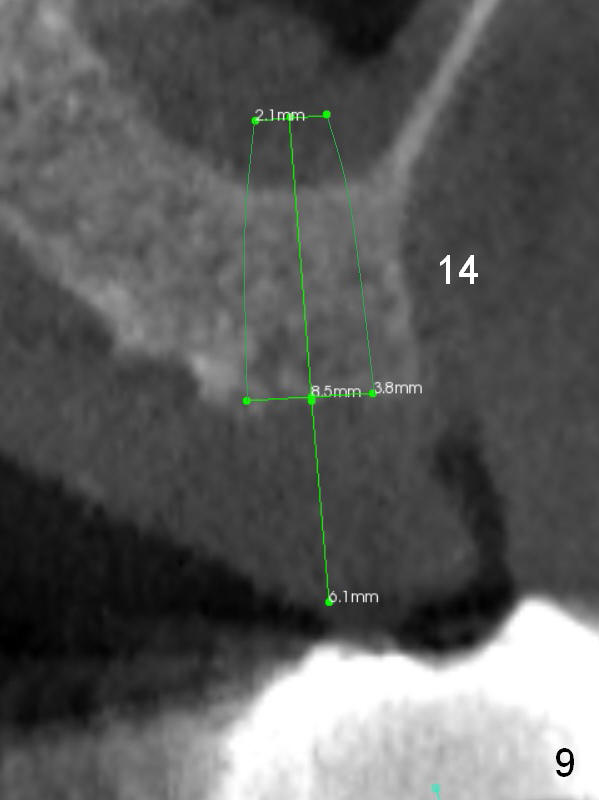

In case primary stability is questionable for example at #15 (Fig.10), consider placing implants at #12 and/or 14 (Fig.7,9).